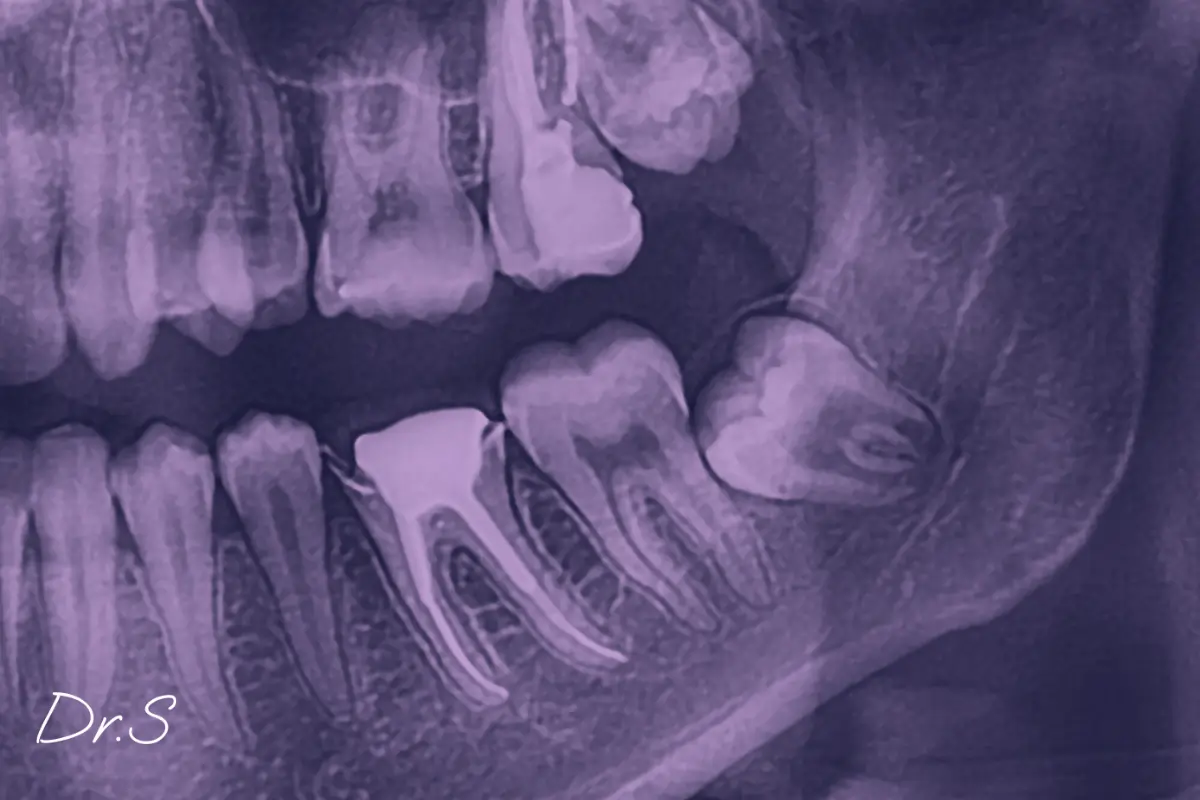

Parfois, on ne les découvre qu’à l’occasion d’un examen radiologique, lors d’un bilan orthodontique ou en lien avec une douleur inexpliquée au fond de la mâchoire.

Les critères reposent souvent sur l’analyse de l’évolution de la dent, sa position, mais aussi les signes cliniques associés. La radiographie 3D est un outil précieux qui permet de préciser les rapports entre la racine et les nerfs situés à proximité.

Une radiographie panoramique à partir de 16-17 ans peut aider à faire le point sur leur présence ou non, et permettre un suivi raisonné.

Oui, l’imagerie 3D ou panoramique dès l’adolescence permet souvent d’observer leur formation bien avant toute éruption visible.